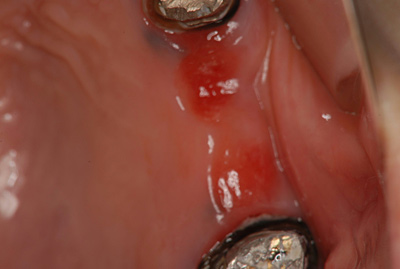

患者さん:大阪市西区 20代女性

オペの内容:右下7番 インプラント 1次オペ

■クライアントさんからの感想: 全く痛くなかったです。

植立位置、方向 共に良好。患者様に満足して頂き、自分としても喜ばしい結果となりました。

治療方法

右下7番をインプラントで治療しました。

費用

今回治療した3本のみの費用です。

インプラント ¥250,000(税抜)

チタンアバットメント ¥60,000(税抜)

オールセラミック冠 ¥100,000(税抜)